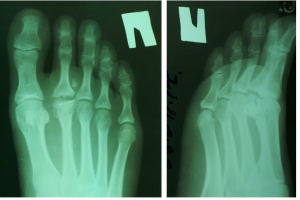

На рентгенограммах визуализируются крупные остеофиты по тыльной поверхности головки и свободные внутрисуставные тела.

Учитывая молодой возраст пациентки и желание в последующем заниматься спортом, запланирована операция - корригирующая тыльная клиновидная остеотомия 2 плюсневой кости правой стопы, резекция экзостозов, удаление свободных внутрисуставных тел, синовэктомия.